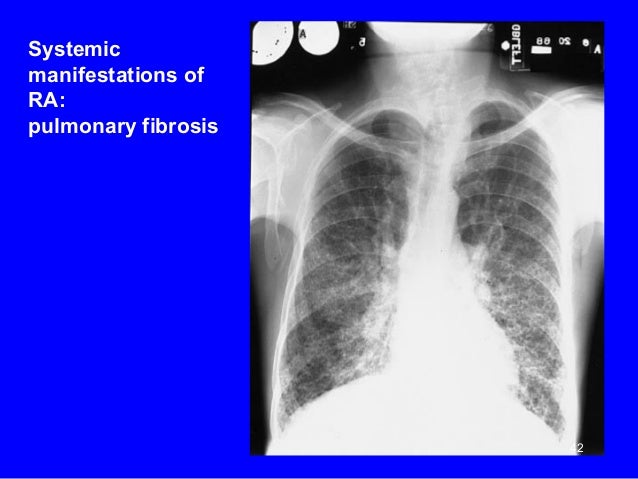

Pulmonary fibrosis is a well recognized extraarticular manifestation of rheumatoid arthritis (ra) 1. Rheumatoid pulmonary vasculitis is rare. Ra causes inflammation and pain that affects the.

Rheumatoid arthritis (ra) is a condition that affects about 1% of the population worldwide. Inflammation from rheumatoid arthritis can lead to pulmonary fibrosis, a serious lung disease. Learn more about how to publish and our partnership with hindawi.

Over time, rheumatoid arthritis can lead to lung tissue damage, which can result in a condition called pulmonary fibrosis. Pulmonary disease also may be observed as a toxic event consequent to tre. One of the patients was misdiagnosed and mismanaged as a patient with pulmonary tuberculosis.

Although the clinical course of many individuals with this disorder can mimic that observed in patients with idiopathic pulmonary fibrosis, the natural history of fibrotic lung disease associated with rheumatoid arthritis remains largely undefined. The pulmonary manifestations of rheumatoid arthritis include pleural effusion, diffuse interstitial fibrosis and pneumonitis, necrobiotic nodules, caplan�s syndrome, pulmonary hypertension out of proportion to interstitial lung disease (pulmonary vascular disease), upper lobe fibrobullous disease, bronchiolitis, and bronchogenic carcinoma. Shared mechanistic and phenotypic traits suggest overlapping disease mechanisms francisco paulin , m.d., 1 tracy j.